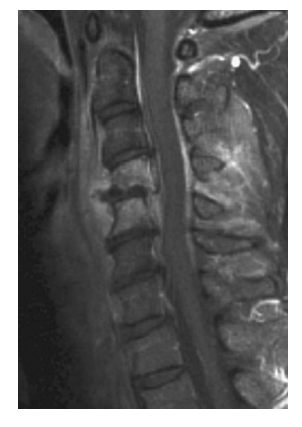

A 39-year-old presents with 4 days of neck pain and unsteady gait. He had recently completed a course of antibiotics for cellulitis. ON examination he was myelopathic, with sensory impairment below C4 level. Reflexes were brisk globally with upgoing plantars. He is pyrexial with a temperature of 38.2 °C. Blood cultures grow Staph aureus. T1 contrast MRI is shown. Which one of the following is

most likely?

b. Epidural abscess

Epidural abscess can result from hematogenous

spread, local extension, or direct inoculation.

This condition is usually found in adults; risk factors include intravenous drug abuse, diabetes

mellitus, prior spine trauma, renal failure, and

pregnancy. The majority of cases are located in

the thoracic spine. Causative organisms are S.

aureus (70%), other staphylococcal species, aerobic streptococci, Enterobacteriaceae (mainly E. coli)

Pseudomonas species mixed bacterial infections

and fungi. The initial presentation includes localized pain and fever with elevation of the ESR,

CRP, and leukocyte count. Blood cultures are

positive in 60% of patients. MRI is able to visualize the degree of cord compression and extent of

abscess in all directions, and discitis/vertebral

osteomyelitis which commonly accompanies it.

Areas of infection have characteristically high signal intensity on T2-weighted image. Without

treatment, significant neurologic deficits occur

and eventually paralysis may develop. Significant

neurologic recovery is observed in patients with

mild neurologic deficits or paralysis of less than

36 h duration who undergo surgical intervention.

Complete paralysis of greater than 36-48 h duration has not shown recovery. The death rate associated with epidural abscess has been reported as 12%. The surgical approach is determined by the location of the epidural abscess. An abscess located posteriorly and extending over multiple levels is best treated by multiple-level laminotomies or laminectomy, taking care to preserve the facet joints. Alternatively, debridement of the spinal canal through fenestrations removing the ligamentum flavum and portions of adjacent lamina, and use of catheters can be considered.